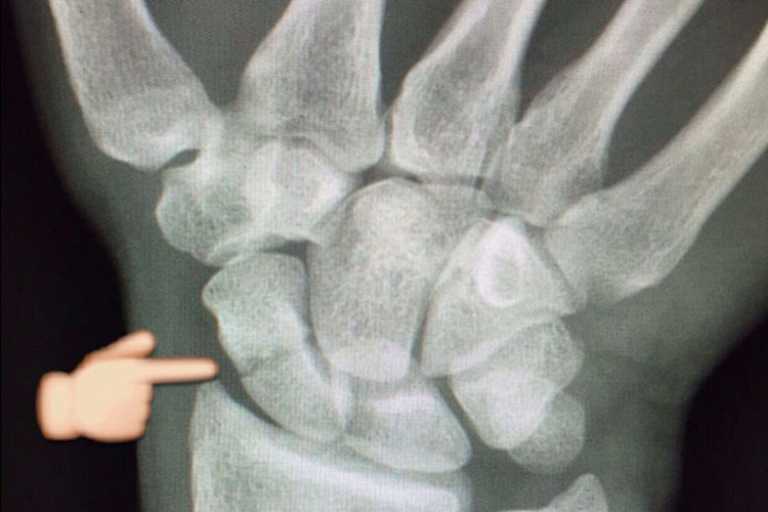

"Aber er dürfte auf Urlaub sein, ich habe ihn nicht erreicht. Ich habe dann viel rumtelefoniert und Kontakt zum Chefarzt des Klinikums Augsburg aufgenommen, der meinem Onkel Max im März 2008 nach einem Motorradunfall den Unterschenkel amputiert hat", erzählte Stefan. "Er hat mich an Dr. med. Stefan Krischak verwiesen, er ist Leiter für Hand- und Plastische Chirurgie. Er wird mich Montagmittag operieren; bei ihm bin ich in guten Händen. Das Röntgenbild zeigt einen glatten Bruch. Man hat mir versichert, das lasse sich gut operieren. Ich war jetzt gerade vier Stunden dort im Krankenhaus, es gab eine Narkosebesprechung und so weiter."